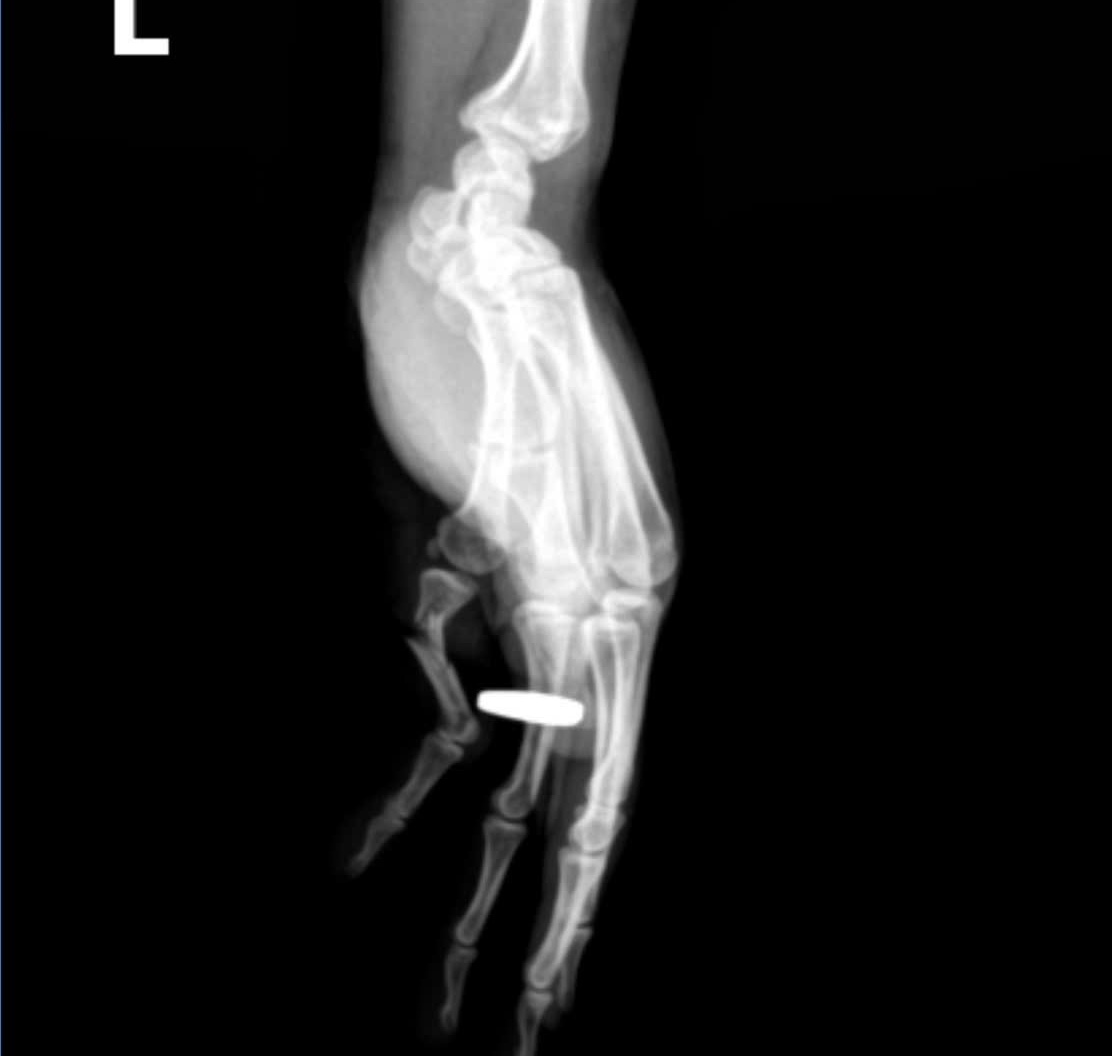

Timely emergency care for open finger fracture due to traffic accident

Timely emergency treatment for open finger fracture due to a traffic accident at Hoe Nhai General Hospital has just been performed.